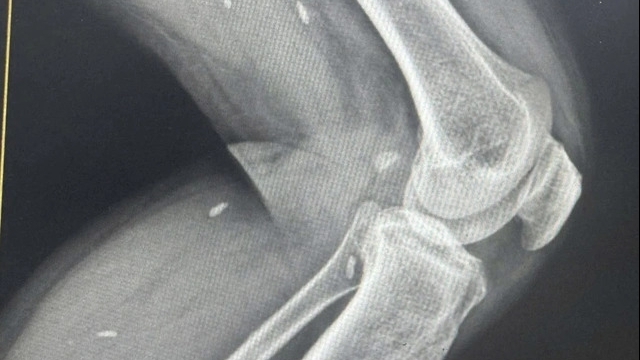

| Ảnh minh họa |